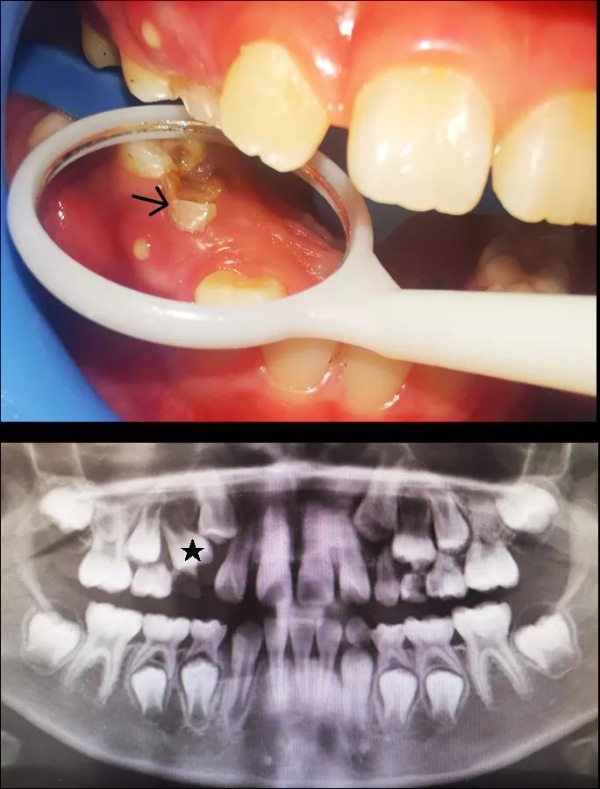

经过检查,王医师确认,小元宝整齐的下前牙内侧确实冒出了两颗“不速之客”,而这正是将来要接替前面两颗乳牙的恒牙。

若恒牙已经萌出了,但相对应的乳牙却没能脱落,就会一起并排留在口腔中,就导致了“双排牙”,专业上称为“乳牙滞留”。

当乳牙的炎症已经波及到了下面的恒牙时,就可能会引起恒牙过早萌出,也可导致双排牙。这种情况下,过早萌出的恒牙牙根还没发育完好,很脆弱,甚至有脱落的风险。

王医生回忆,之前门诊来过一位7岁的小朋友,右上排一个乳牙牙冠已经完全蛀掉。询问家长得知,来就诊的之前几个月,小朋友就已经因为这颗牙齿感染发烧过两次,烧退后也一直未处理该牙。

后来因为发现这颗牙齿旁边疑似有新牙长出,才来医院就诊。医生检查发现,孩子的这部分牙龈已经有脓液溢出了,而影像学检查提示上方正在萌出的恒牙牙根才刚刚开始发育——这样的双排牙很可能一个也保不住。